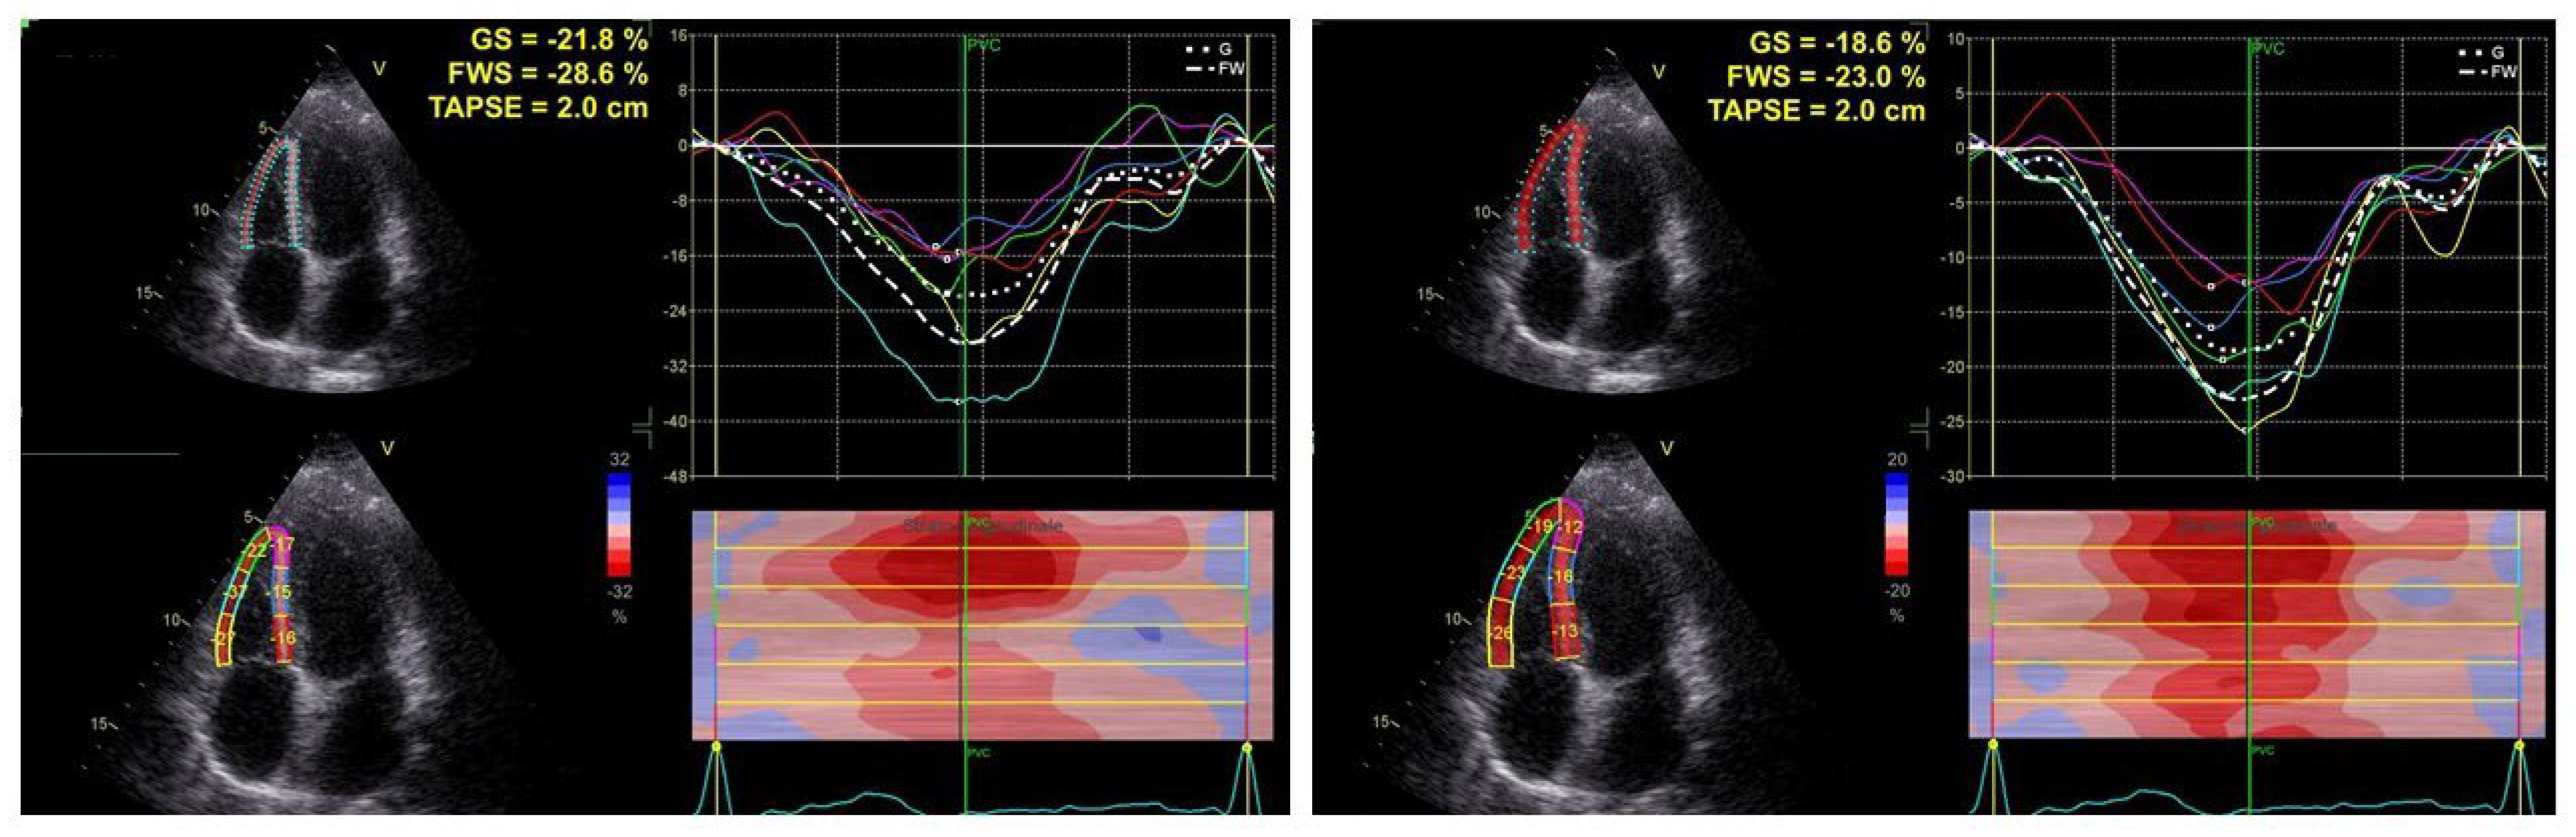

2.2. Echocardiographic Examination

| RV-GLS (%) | 20 (19–22) | 24 (22–27) | 0.0001 |

| TAPSE/sPAP (mm/mmHg) | 0.60 (0.24–1.10) | 0.84 (0.39–1.32) | 0.0001 |

| RV-GLS/sPAP (%/mmHg) | 0.55 (0.47–0.67) | 0.92 (0.77–1.07) | 0.0001 |